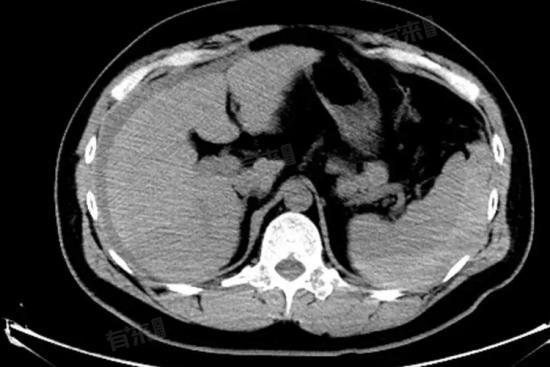

脾内钙化灶是在进行医学影像检查时发现的一种表现,是指在脾脏组织内出现的钙盐沉积,表现为影像学上的高密度影,形成原因较为复杂,可能是由于多种因素引起的。

- 如果脾内钙化灶较小,患者无任何症状,且其他检查结果正常,医生通常会建议观察随访。定期进行医学影像检查,如超声、CT 等,观察钙化灶的大小、形态是否发生变化。如果钙化灶一直保持稳定,无需进行特殊处理。